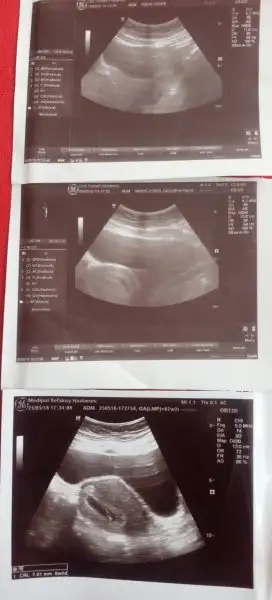

Ben miniğimizi 5+5 te gördüm, kalp ritmini de ekrandan gördük ama duymadık. 10 gün sonra kontrole gittiğimizde onu da duyduk6. haftadan itibaren mide bulantılarım başladı ve hala devam ediyor. Zaten hassas burunlu birisiydim şimdi milyonlarca koku duyuyorum her an:) Keza kasık ağrılarımda ara ara devam ediyor. En yoğun kasık ağrısı dönemim 4 ve 6. haftalar arasıydı. Doktorum yürüyüşü ihmal etme dedi. Günde yavaş yavaş yarım saat yürüyorum. Bir sonraki kontrol 12. haftada. İlk üç ayı bitirdikten sonra bizler için biraz daha farklı bir süreç başlayacakmış. Bebek artık depomuzdan kullanmayacak vücudumuzdan direk beslenecek bu yüzden demir-kalsiyum-protein vs. eksikliği yaşanabilirmiş. Vitaminlerle dengeleyeceğiz artık.